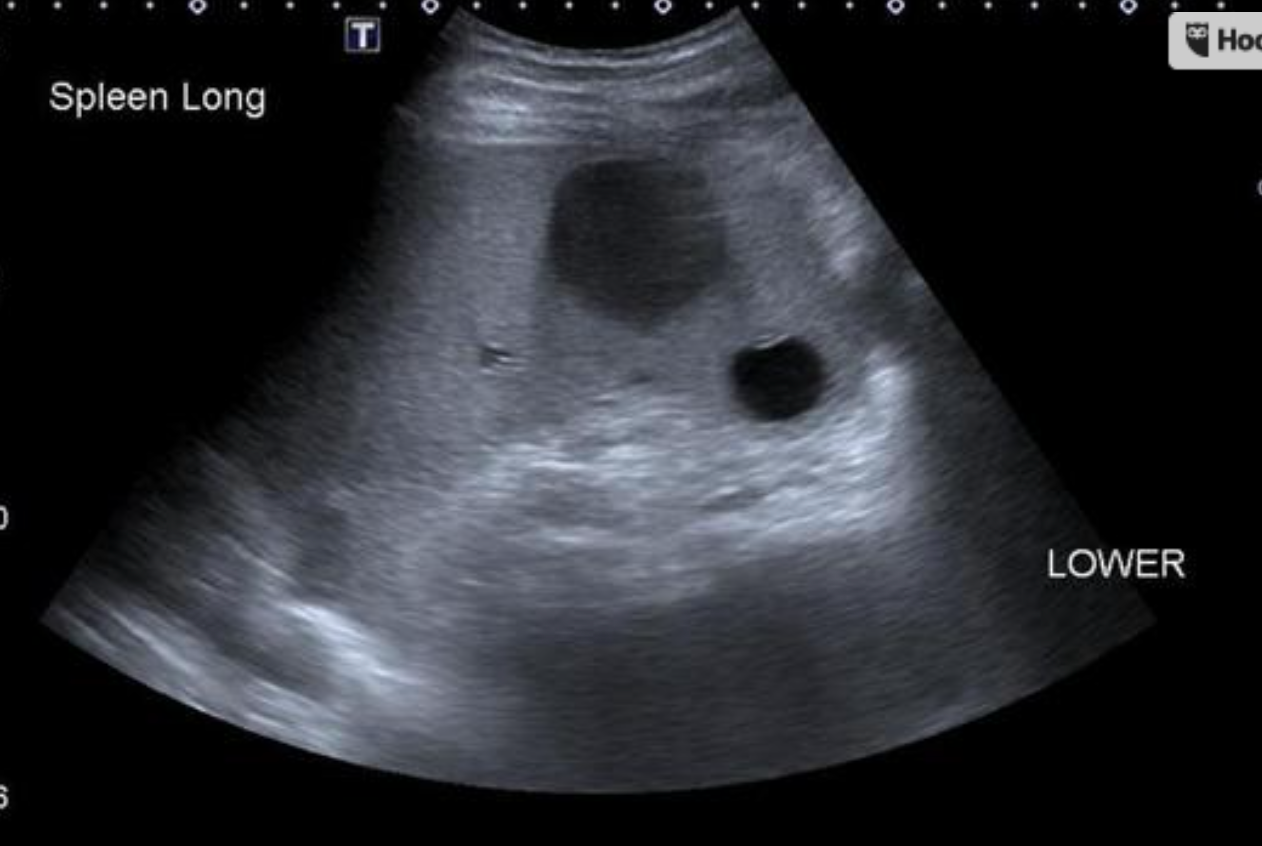

Tc-99m-tagged heat-damaged RBC scan (Tc-99m-DRBC) with autologous erythrocytes shows accumulation in the abdominal cavity, consistent with intra-abdominal splenosis.

Case Discussion

Main concern for intra-abdominal lesions found on CT scan was for metastatic disease. Using heat treated RBC confirmed the functioning splenosis at the various abdominal sites.